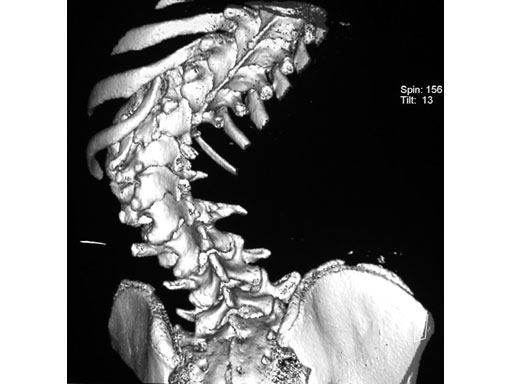

Case provided by Cornelius Wimmer, Vogtareuth, Germany

A 23-year-old man with neurogenic kyphoscoliosis, Cobb angle: 120. Fusion of T7S1 with universal reduction screws. Duration of surgery: 4.5 hours.